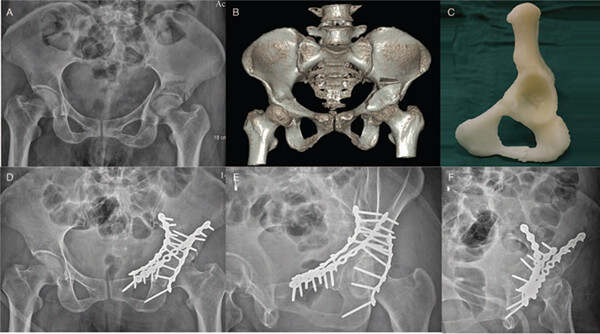

骨折碎片的3D模型。圖片來自《中華醫(yī)學雜志》。

為了開展研究,研究小組在2013年9月至2017年9月之間對40例被診斷為雙柱髖臼骨折的患者進行了一項隨機前瞻性病例對照研究。20位患者被分配到3D打印組,其他20位患者被分配使用塊隨機化的常規(guī)方法組。用于骨折碎片的虛擬仿真和3D打印模型的方法涉及將每個患者骨盆的地形圖像保存為醫(yī)學數(shù)字成像和通信(DICOM)文件。然后將它們導入由Materialise開發(fā)的醫(yī)學3D圖像處理軟件MIMICS。使用重新定位功能在解剖學上減少了骨折碎片,然后將其作為STL文件導出,并導入Materialize Magics軟件中以進行固定和支撐生成。

3D打印組中一種情況的圖像。圖片來自《中華醫(yī)學雜志》。

然后將最終的STL進行3D打印,并用于對手術板進行預輪廓處理,并使用3D打印的縮小型半骨盆模型測量螺釘?shù)拈L度。在外科手術模擬之后,對預先輪廓化的解剖板和螺釘進行消毒,并用于髖臼外科手術。